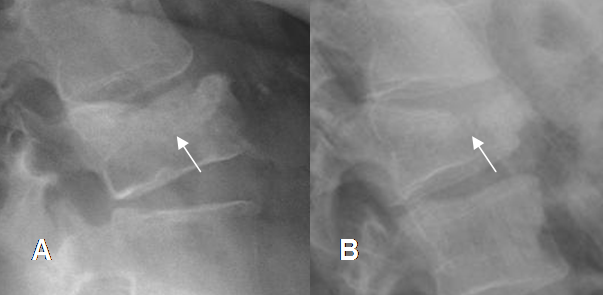

Fig 213. Fractura aguda.

A y B: Rx lateral. Pérdida en la nitidez de las placas superiores y aumento de la densidad, por fracturas impactadas de evolución aguda.

Fig 214. Fractura aguda.

A y B: Rx lateral. Pérdida de la nitidez de las placas superiores, por fracturas de evolución aguda.